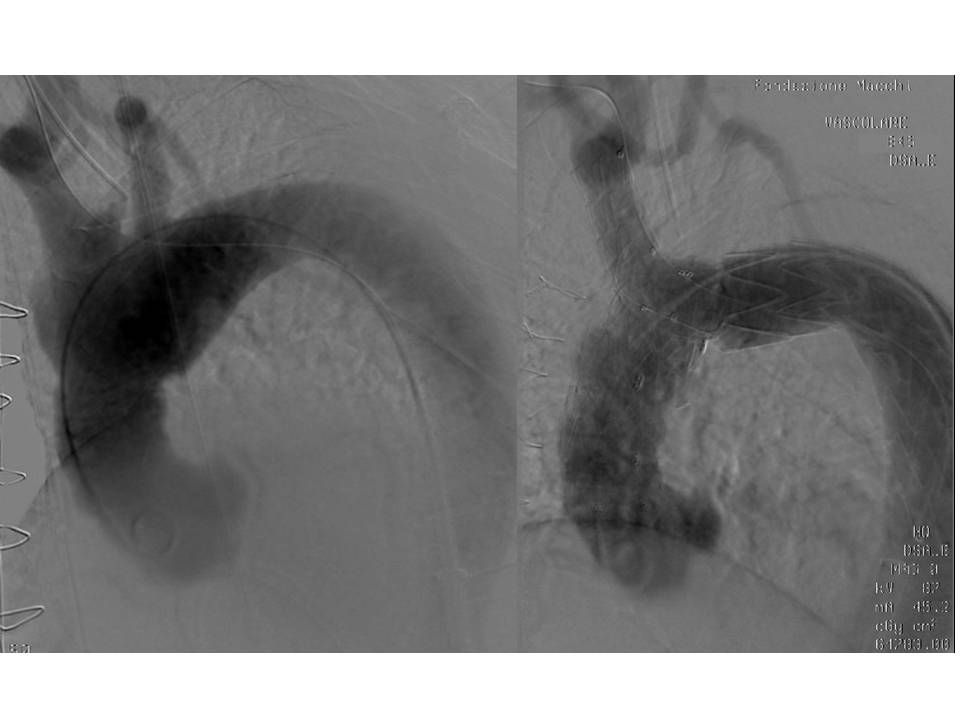

Solo a quel punto, insieme ai radiologi interventisti, si è potuti passare ad inserire per via endovascolare la protesi ramificata nel tratto dell'aorta ascendente e dell'arco, un segmento in cui è massima la pressione esercitata dal sangue in uscita dal cuore e le cui pareti si dilatano e si contraggono in sintonia con il ritmo cardiaco.

"Queste protesi sono state studiate per adattarsi al meglio anatomicamente alle sollecitazioni emodinamiche così vigorose in questo primo tratto di aorta toracica’ – continua Piffaretti – Per ridurre tali interferenze indotte dal battito cardiaco e dalla spinta pressoria, e quindi per ottimizzare il posizionamento dell’endoprotesi limitando il rischio di interferire con l’origine delle arterie coronarie o ledere la valvola aortica, è necessario che l’impianto eseguito a quattro mani dal chirurgo vascolare e dal radiologo interventista sia accompagnato in quella fase delicatissima da una fibrillazione cardiaca indotta e regolata dal cardiologo tramite il pace-maker temporaneo".

Entrambi gli interventi sono riusciti perfettamente sotto il profilo tecnico e clinico. Alle delicate fasi intraprocedurali gestite impeccabilmente sotto il profilo anestesiologico dai Dott. Luca Guzzetti e Dott.ssa Dunia D’Onofrio dell’equipe del Dott. Alessandro Bacuzzi, hanno fatto seguito alcuni giorni trascorsi nelle Terapie Intensive del nostro Ospedale, quella Cardiochirurgica del Prof. Paolo Severgnini e quella Multidisciplinare del Prof. Luca Cabrini, dove sono state ottimizzate le fasi immediatamente post-chirurgia prima del rientro in reparto di degenza.